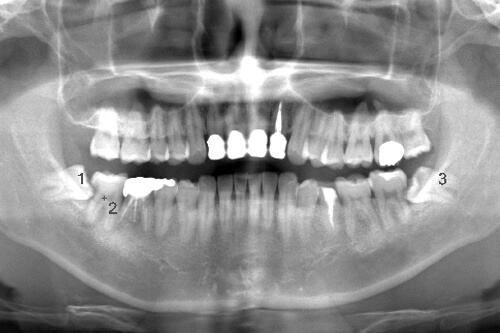

CASE 2

| 主訴 | 左上下親知らず抜きたい |

| 抜歯期間 | 30分 |

| 抜歯費用 | 約2,500円(保険内) 別途CT撮影で3,000円 |

| 抜歯内容 | 左上下の親知らず抜歯 |